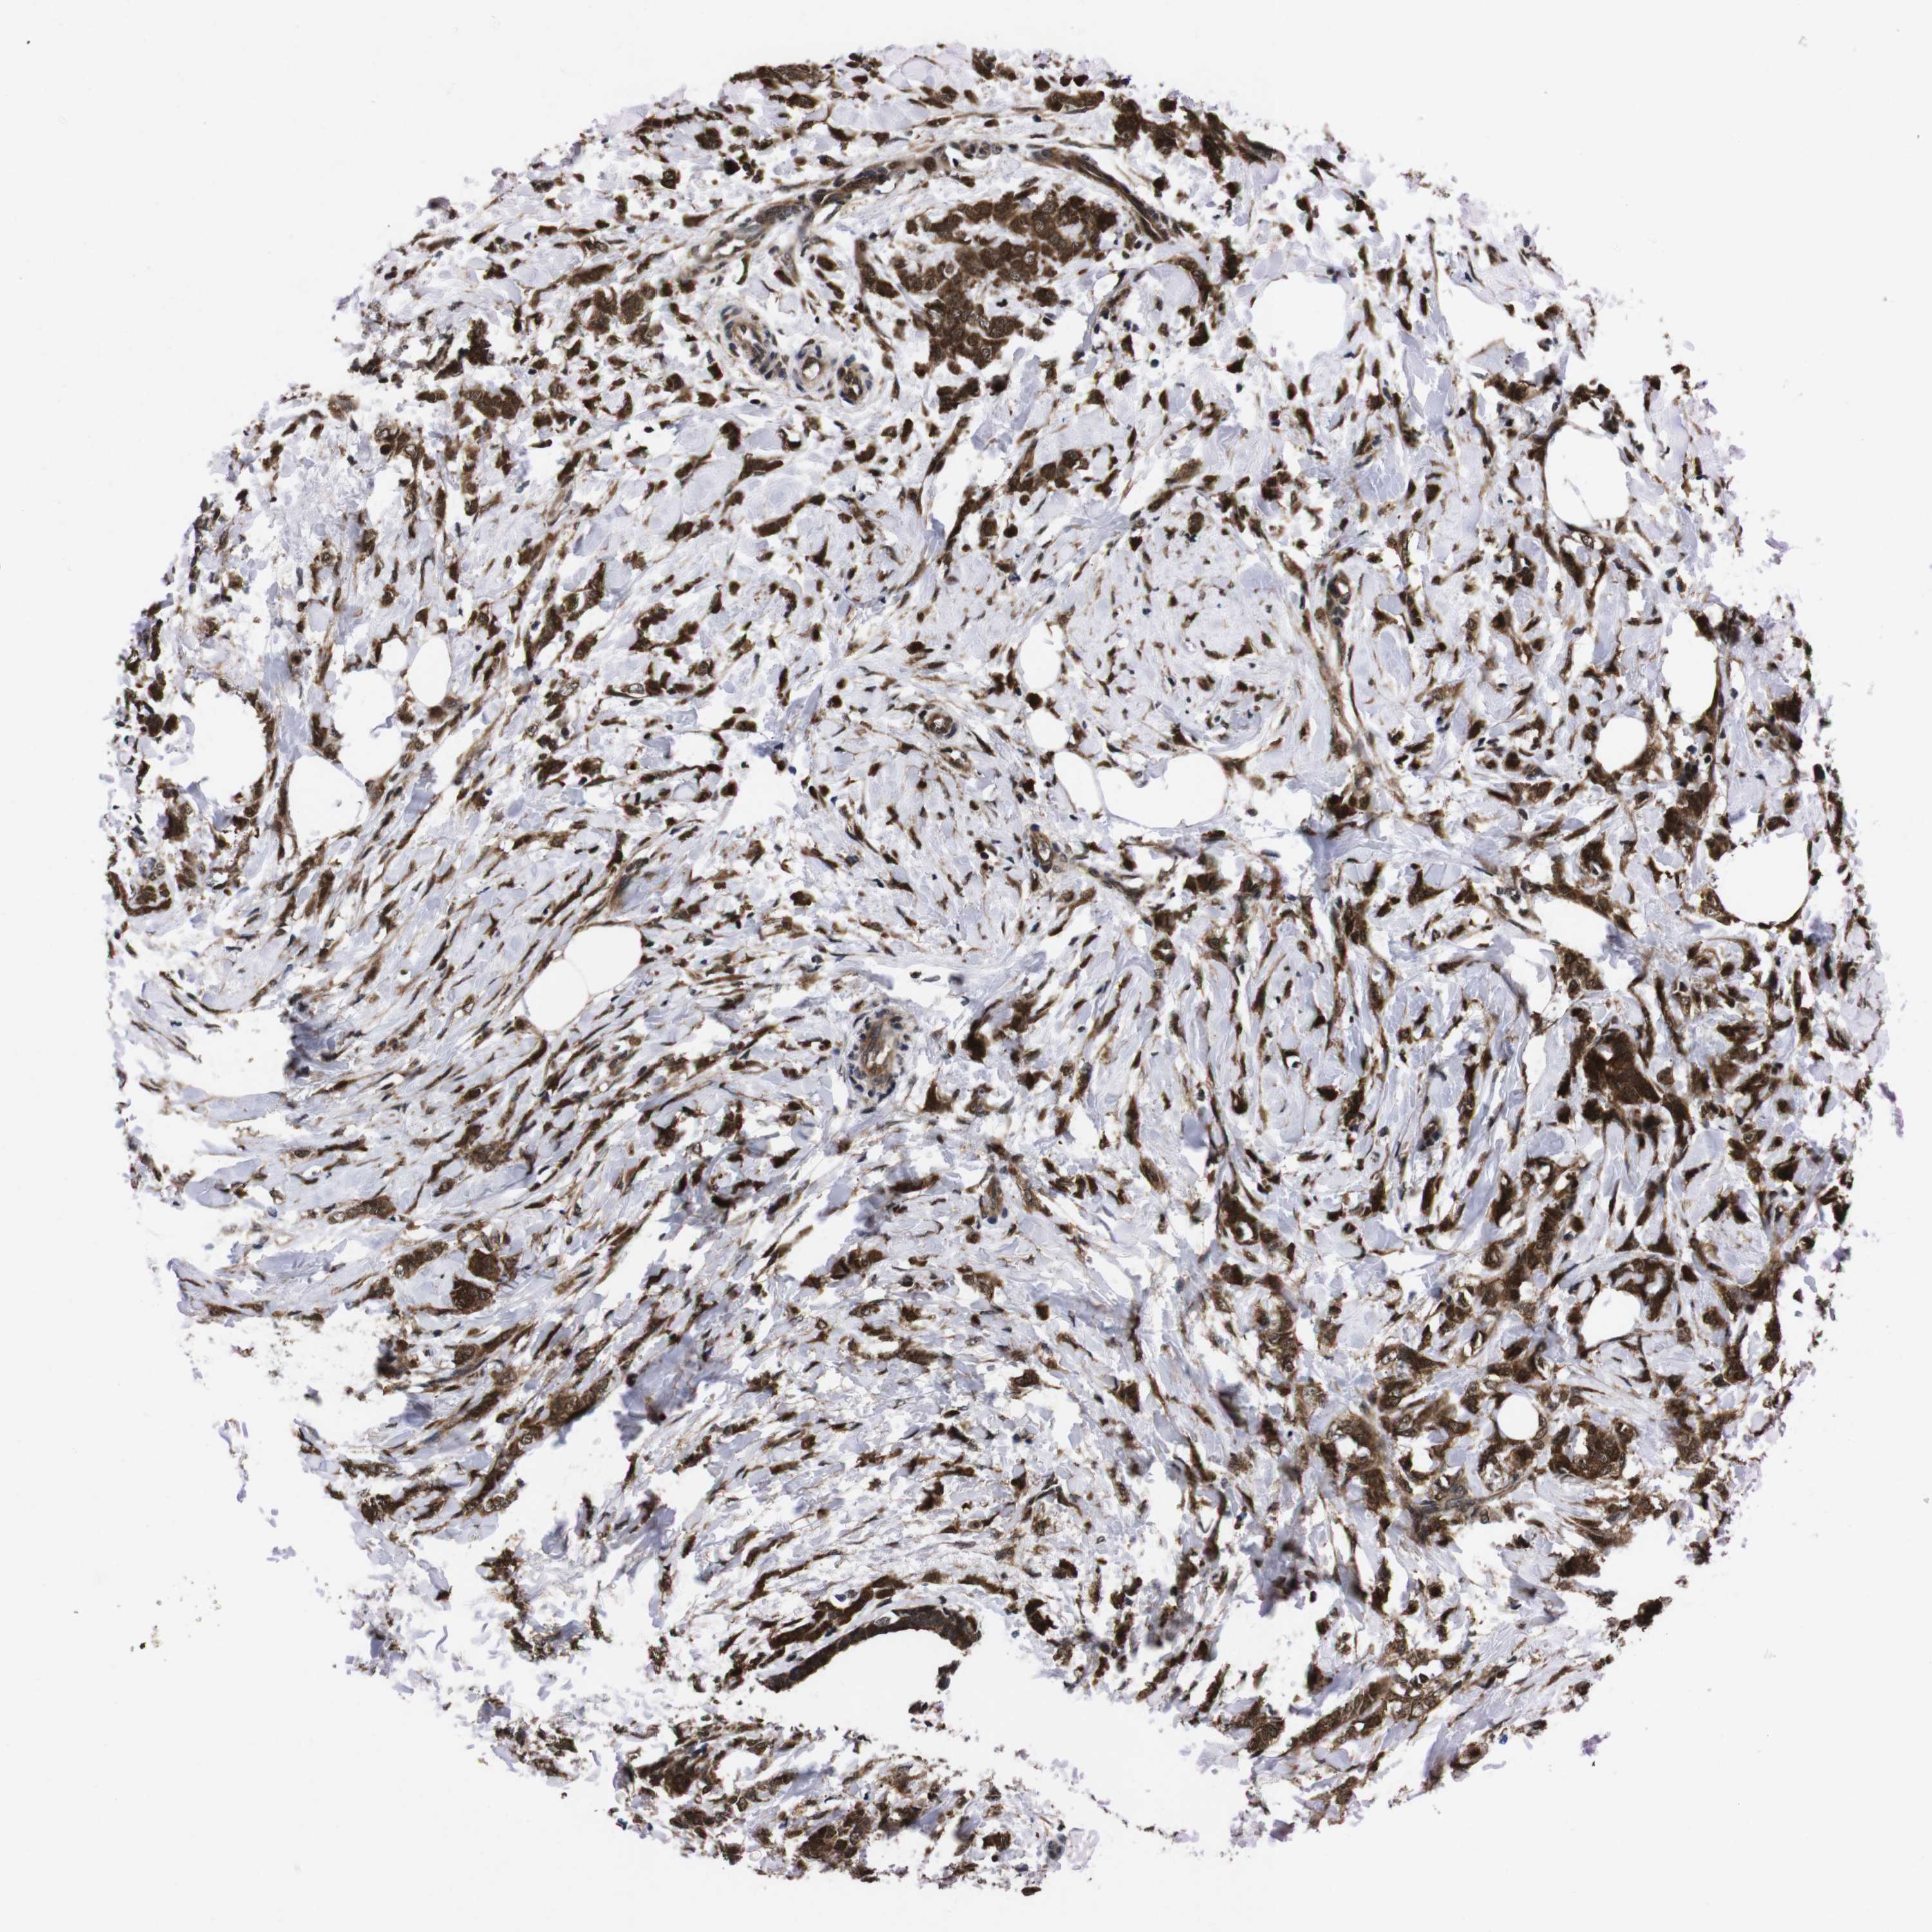

BRCA TCGA BRCA VALIDATION PROTEIN EXPRESSION